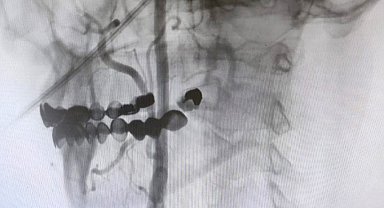

Manisa Şehir Hastanesi'nde felç riskine karşı ameliyatsız çözüm

Teknede kopan parmak ameliyatla kurtarıldı